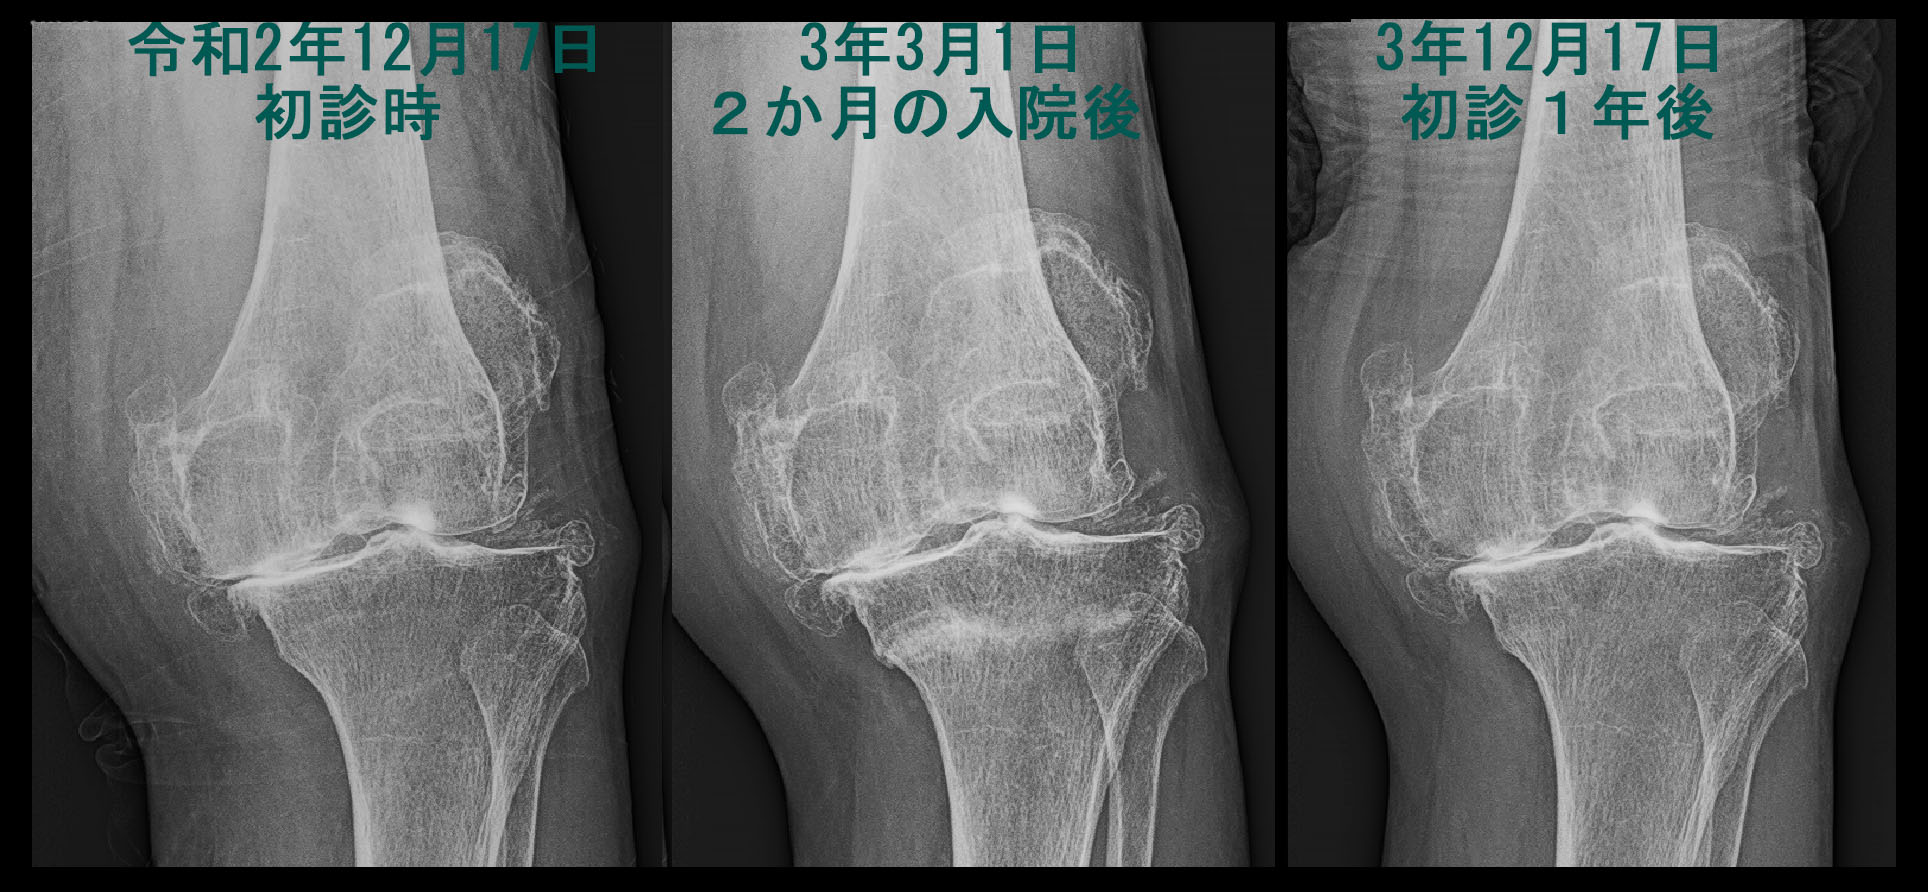

初診時からのレントゲン像を並べてみます。

84才経過Xp.jpg

元々重度の変形性膝関節症があり、圧痛は左脛骨(下腿側の骨です)の赤矢印部分(内顆部)に確認されました。通常、変形性膝関節症の場合、圧痛は大腿骨と脛骨の隙間の部分にみられることが多いのですが、脛骨の内顆部の圧痛であったこと、痛みが発症すると直ぐにタクシー代を払って受診していることを考慮すると、初診時から骨の異常の可能性を考慮してMRI検査をするべきだったのかもしれません。しかし、この時は痛み止めを処方して経過観察としました。

次のレントゲン像は同年の年末12月28日に10日前からの左膝痛が増悪した時の者をです。リハ退院時に確認されたしっかりとした仮骨はまったく確認できません。これはどういうことなのでしょうか。